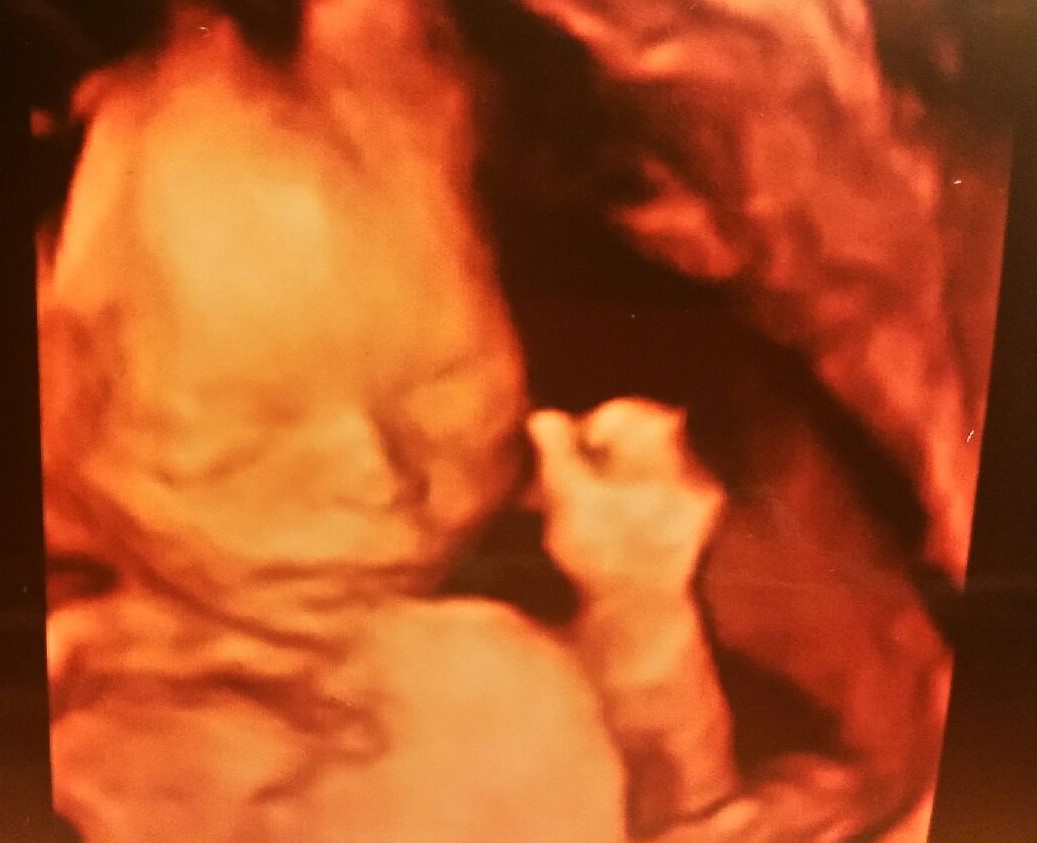

Personhood Education

THE NEW PRO-LIFE PARADIGM FOR THE 21ST CENTURY